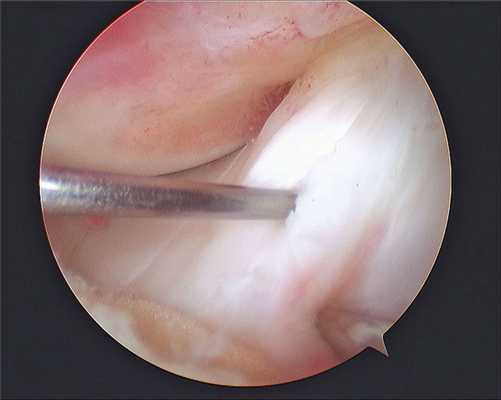

Все артроскопические вмешательства выполняют под визуальным контролем. Для визуализации внутрисуставных структур в суставную полость вводят артроскоп, который представляет собой жестко соединенные между собой трубку и окулярный оголовок. Изображение из артроскопа выводится на экран в операционной, что позволяет хирургу контролировать свои действия, а пациенту — наблюдать за ходом хирургического вмешательства.

Сначала ногу пациента сгибают и через небольшой разрез вводят канюлю. Затем — разгибают и через канюлю вводят артроскоп. Инструменты для артроскопических манипуляций вводят через небольшие разрезы длиной 4-5 мм. После операции артроскоп и все инструменты извлекают, а послеоперационные раны зашивают и заклеивают лейкопластырем.